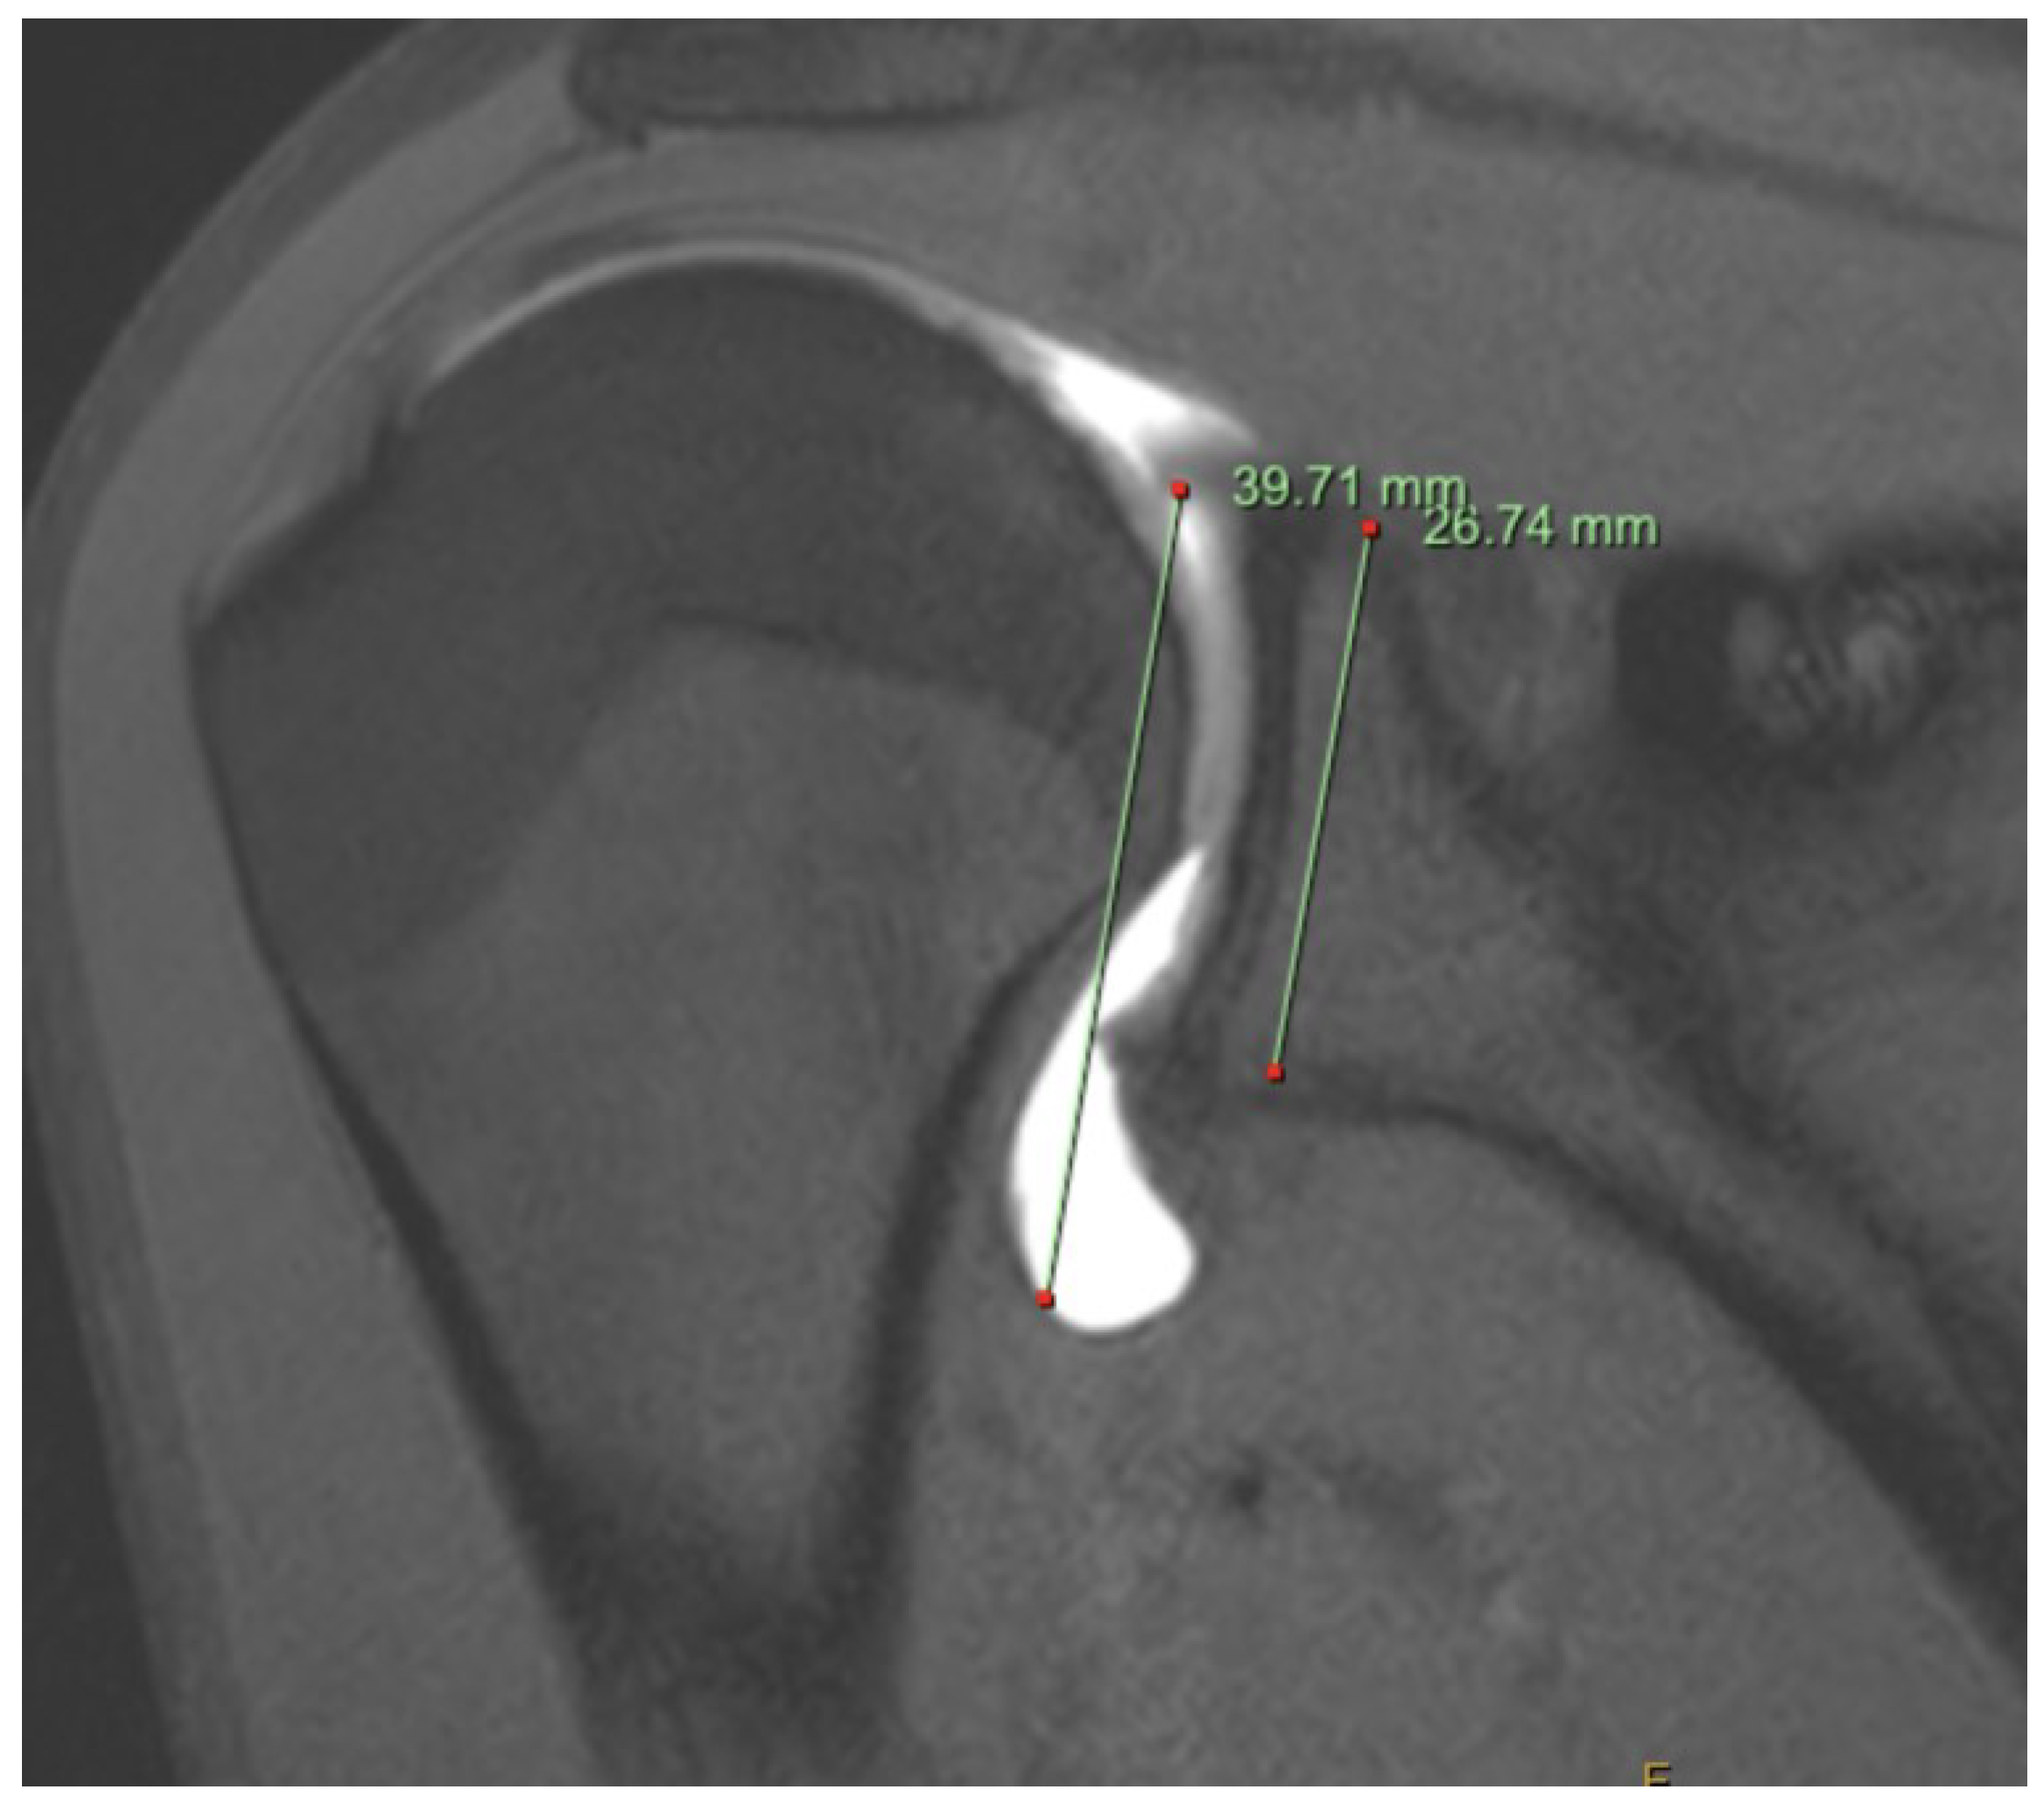

MR arthrogram can be useful for assessment of possible MDI. The gleno-capsular ratio (GC) can be assessed on arthrogram by measuring the distance between the most superior aspect of the glenoid to the most inferior aspect of the capsule and dividing that by the distance between the most superior aspect of the glenoid to the most inferior aspect of the glenoid [35]. It is an indicator of the size of the inferior capsule. MDI should be suspected in patients with a GC > 1.42 with a sensitivity and specificity of 92.3 and 89.2% respectively [35]. An inferior labrocapsular distance, or the distance from the inferior glenoid to the inferior capsule, of over 16.88mm can also be used to screen for MDI on arthrogram with a sensitivity of 77% and a specificity of 96%[36]. Rotator intervals with a width greater than 15.2mm and a depth of greater than 6.4mm may also suggest MDI, with a sensitivity and specificity of 81% and 92% [37].

Figure 1. MR arthrogram of patient with symptomatic MDI. The gleno-capsular ratio is recorded as 1.48.